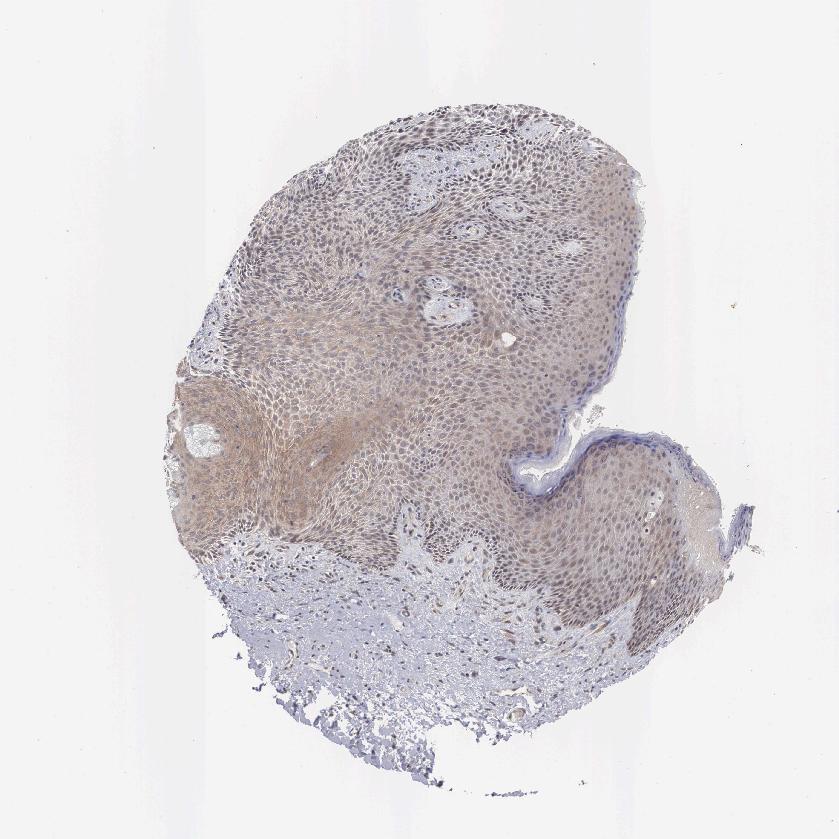

SKIN 1 - Antibody stainingi

Antibody staining in the annotated cell types in the current human tissue is reported as not detected, low, medium, or high, based on conventional immunohistochemistry profiling in selected tissues. This score is based on the combination of the staining intensity and fraction of stained cells.

Each image is clickable and will lead to virtual microscopy that enables deeper exploration of all samples and also displays staining intensity scores, fraction scores and subcellular localization as well as patient and tissue information for each sample.

Antibody HPA000633

Langerhans Not detected

Fibroblasts Not detected

Keratinocytes Not detected

Melanocytes Not detected

SKIN 2 - Antibody stainingi

Epidermal cells Medium